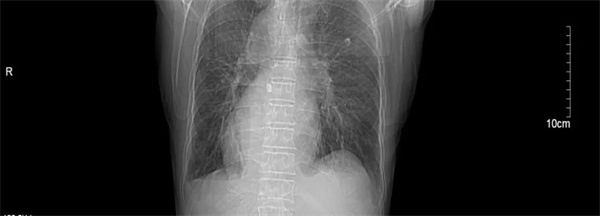

汪大爷因“反复胸闷气喘1周伴头昏”在当地卫生院就诊,心电图检查显示高度-III度房室传导阻滞(心室率40次/分)和镜像右位心心电图。由医共体转诊中心转至我院进一步诊治。入院后,行24小时动态心电图和心脏彩超检查发现,患者不仅患有II度房室传导阻滞,呈2:1下传(最慢心率35次),交界性逸搏伴干扰性房室分离。彩超更是发现汪大爷还是一位罕见的镜面右位心,其心脏及腹腔内脏器官位置与正常人完全相反,如同正常脏器的 “镜中像”,这种先天性畸形的发生几率约为1/100万。

汪大爷最终被诊断为高度房室传导阻滞、镜面右位心和慢性心衰,病情十分危险。心血管内科团队评估后认为,若不及时植入心脏起搏器,汪大爷随时面临心衰加重和猝死的风险。尽管心脏起搏器植入术在池州市第二人民医院是常规手术,但为“镜面人”实施手术难度却极高。医生需要将手术习惯和技巧进行180度“转位”,这不仅要求医生有过硬的基本功和扎实的理论基础,还需对解剖结构和影像学检查熟练掌握,否则稍有不慎就会造成严重的脏器损伤。